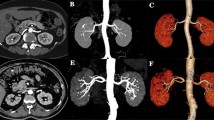

The three image data sets (i.e., FBP, AIDR3D, and FIRST) and the conventional angiography from 30 patients were presented in a random order to two radiologists (K.F. and Y.H., with 9 years of experience and 24 years of experience, respectively). The radiologists were not given access to patient information. CT images were evaluated according to the degree of overall visualization of the cystic artery using a four-point scale. A four-point scale was designed for the image assessment; 1 = poor image quality, obscure origin of cystic artery; 2 = fair image quality, notable blurring of luminal boundaries; 3 = good image quality, minor blurring of luminal boundaries; and 4 = excellent image quality, sharp continuous luminal boundaries at more peripheral branches (Fig. 2).

Figure 4 shows coronal CT images of the superficial branch of the cystic artery in an 83-year-old woman with FBP, AIDR3D, and FIRST (Fig. 4a–c) and 3D maximum intensity projection (MIP) images (Fig. 4d–f: not evaluated in this study) and conventional angiography (Fig. 4g). Coronal CT image and 3D MIP image with FIRST allow the best visualization of the cystic artery compared to FBP and AIDR3D.

Coronal CT images of the superficial branch of the cystic artery in an 83-year-old woman with FBP, AIDR3D, and FIRST (Fig. 4a–c) and 3D maximum intensity projection (MIP) images (Fig. 4d–f) and conventional angiography (Fig. 4g). Coronal CT image and 3D MIP image with FIRST allow the best visualization of the cystic artery compared to FBP and AIDR3D